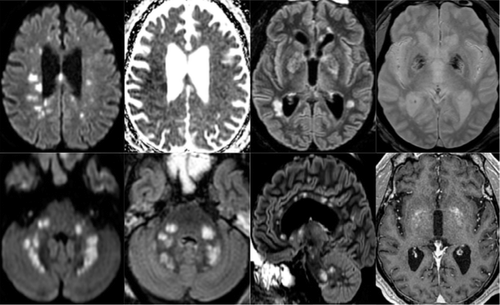

CT and MRI scans show neurological impacts.

Case of acute necrotizing encephalopathy could be first of many.